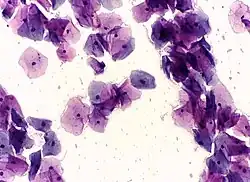

Conventional Pap smear

In the conventional Pap smear, the collected cells are smeared on a microscope slide, and a fixative is applied. The slide is evaluated in a pathology lab to identify cellular abnormalities.